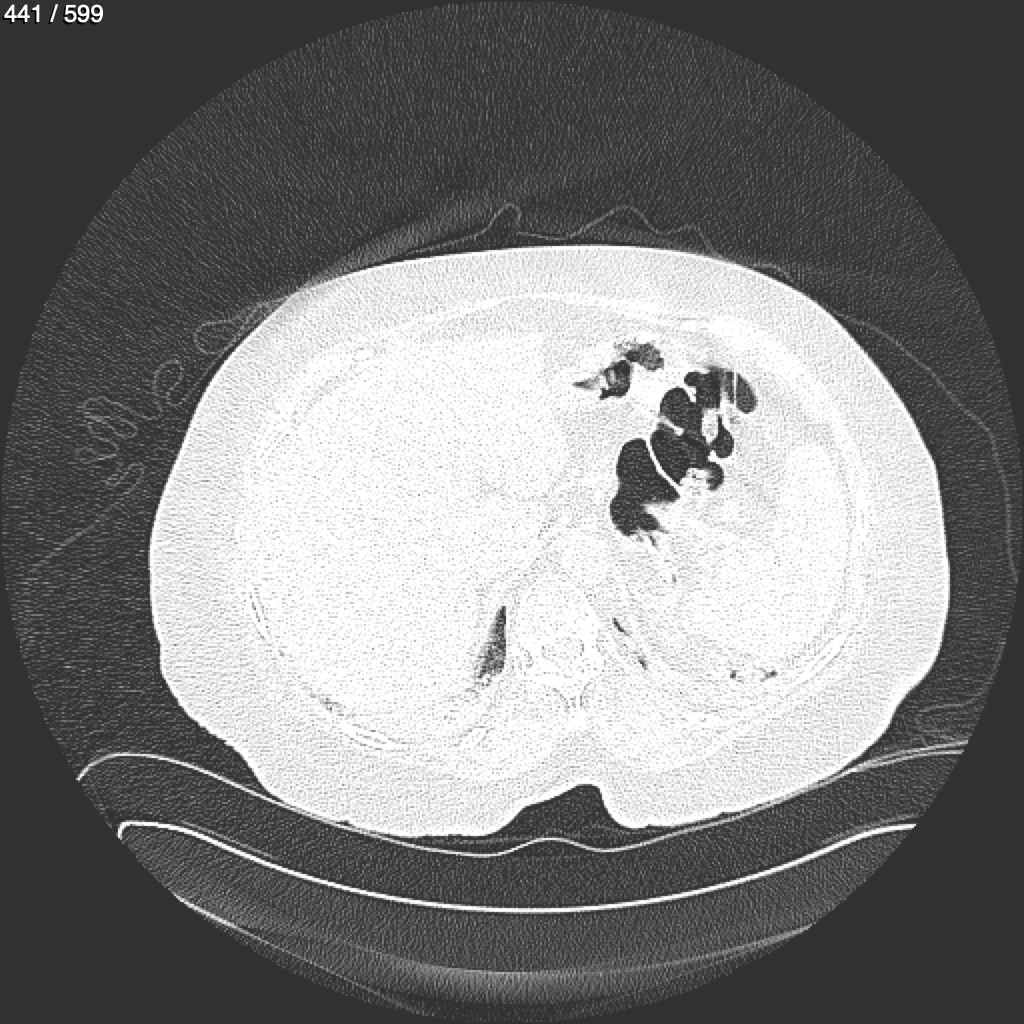

Home G​l​o​r​i​a​ ​G​l​a​d​y​s​ ​B​e​a​s​l​e​y​ ​-​ ​T​ó​r​a​x​ ​T​o​r​a​x​_​S​i​m​p​l​e​ ​(​A​d​u​l​t​o​)